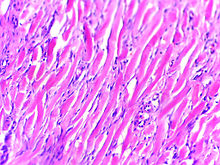

Histologically, keloids are fibrotic tumors characterized by a collection of atypical fibroblasts with excessive deposition of extracellular matrix components, especially collagen, fibronectin, elastin, and proteoglycans. Generally, they contain relatively acellular centers and thick, abundant collagen bundles that form nodules in the deep dermal portion of the lesion. Keloids present a therapeutic challenge that must be addressed, as these lesions can cause significant pain, pruritus (itching), and physical disfigurement. They may not improve in appearance over time and can limit mobility if located over a joint.